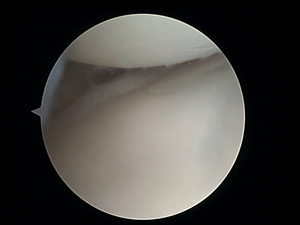

Entrance

To perform wrist arthroscopy, the instruments will have to be inserted in the wrist. The surgeon will start by making a small incision for creating a so-called portal. The different portals will be further discussed in the next section.[2] After the incision has been made, the portal is used to insert a scope. This scope will provide the visualization. In that way, the surgeon will be able to orient within the joint of the wrist. Once a clear view of the wrist is obtained, a possible problem can be identified. This problem, for example a TFCC lesion, may then immediately be solved by operative treatment.